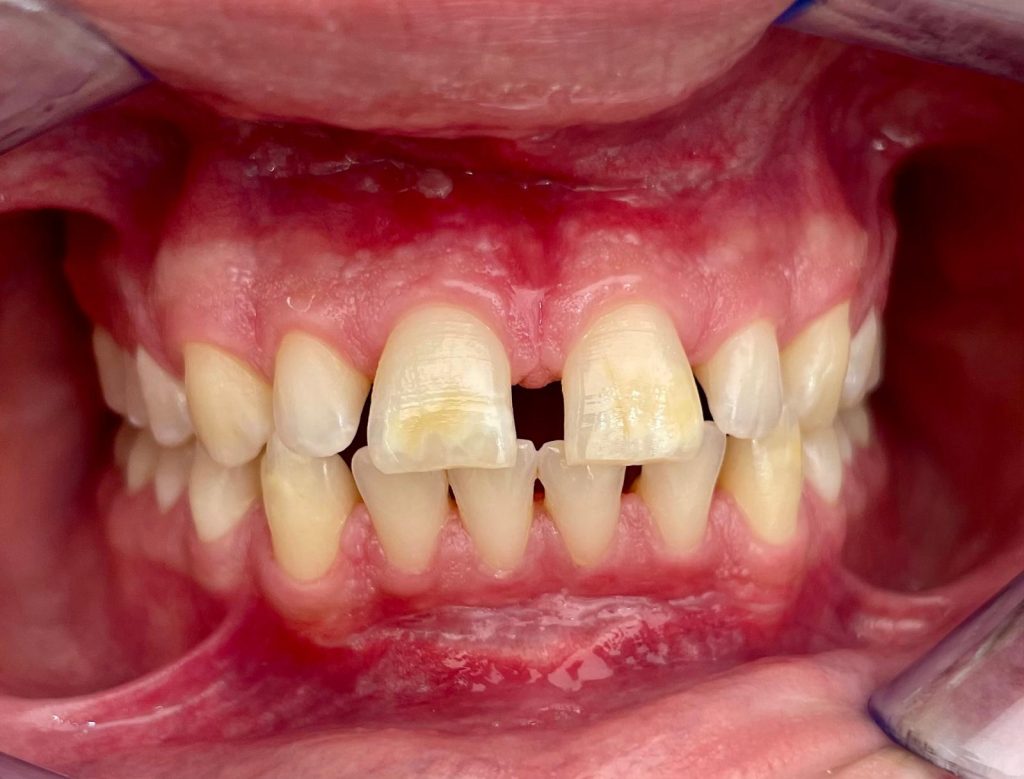

Questa settimana vi presentiamo il caso di frenulectomia del labbro superiore e inferiore eseguita con un laser KTP.

Nelle immagini, oltre alle fasi dell’intervento, è possibile osservare la guarigione dei tessuti dopo 10 giorni.